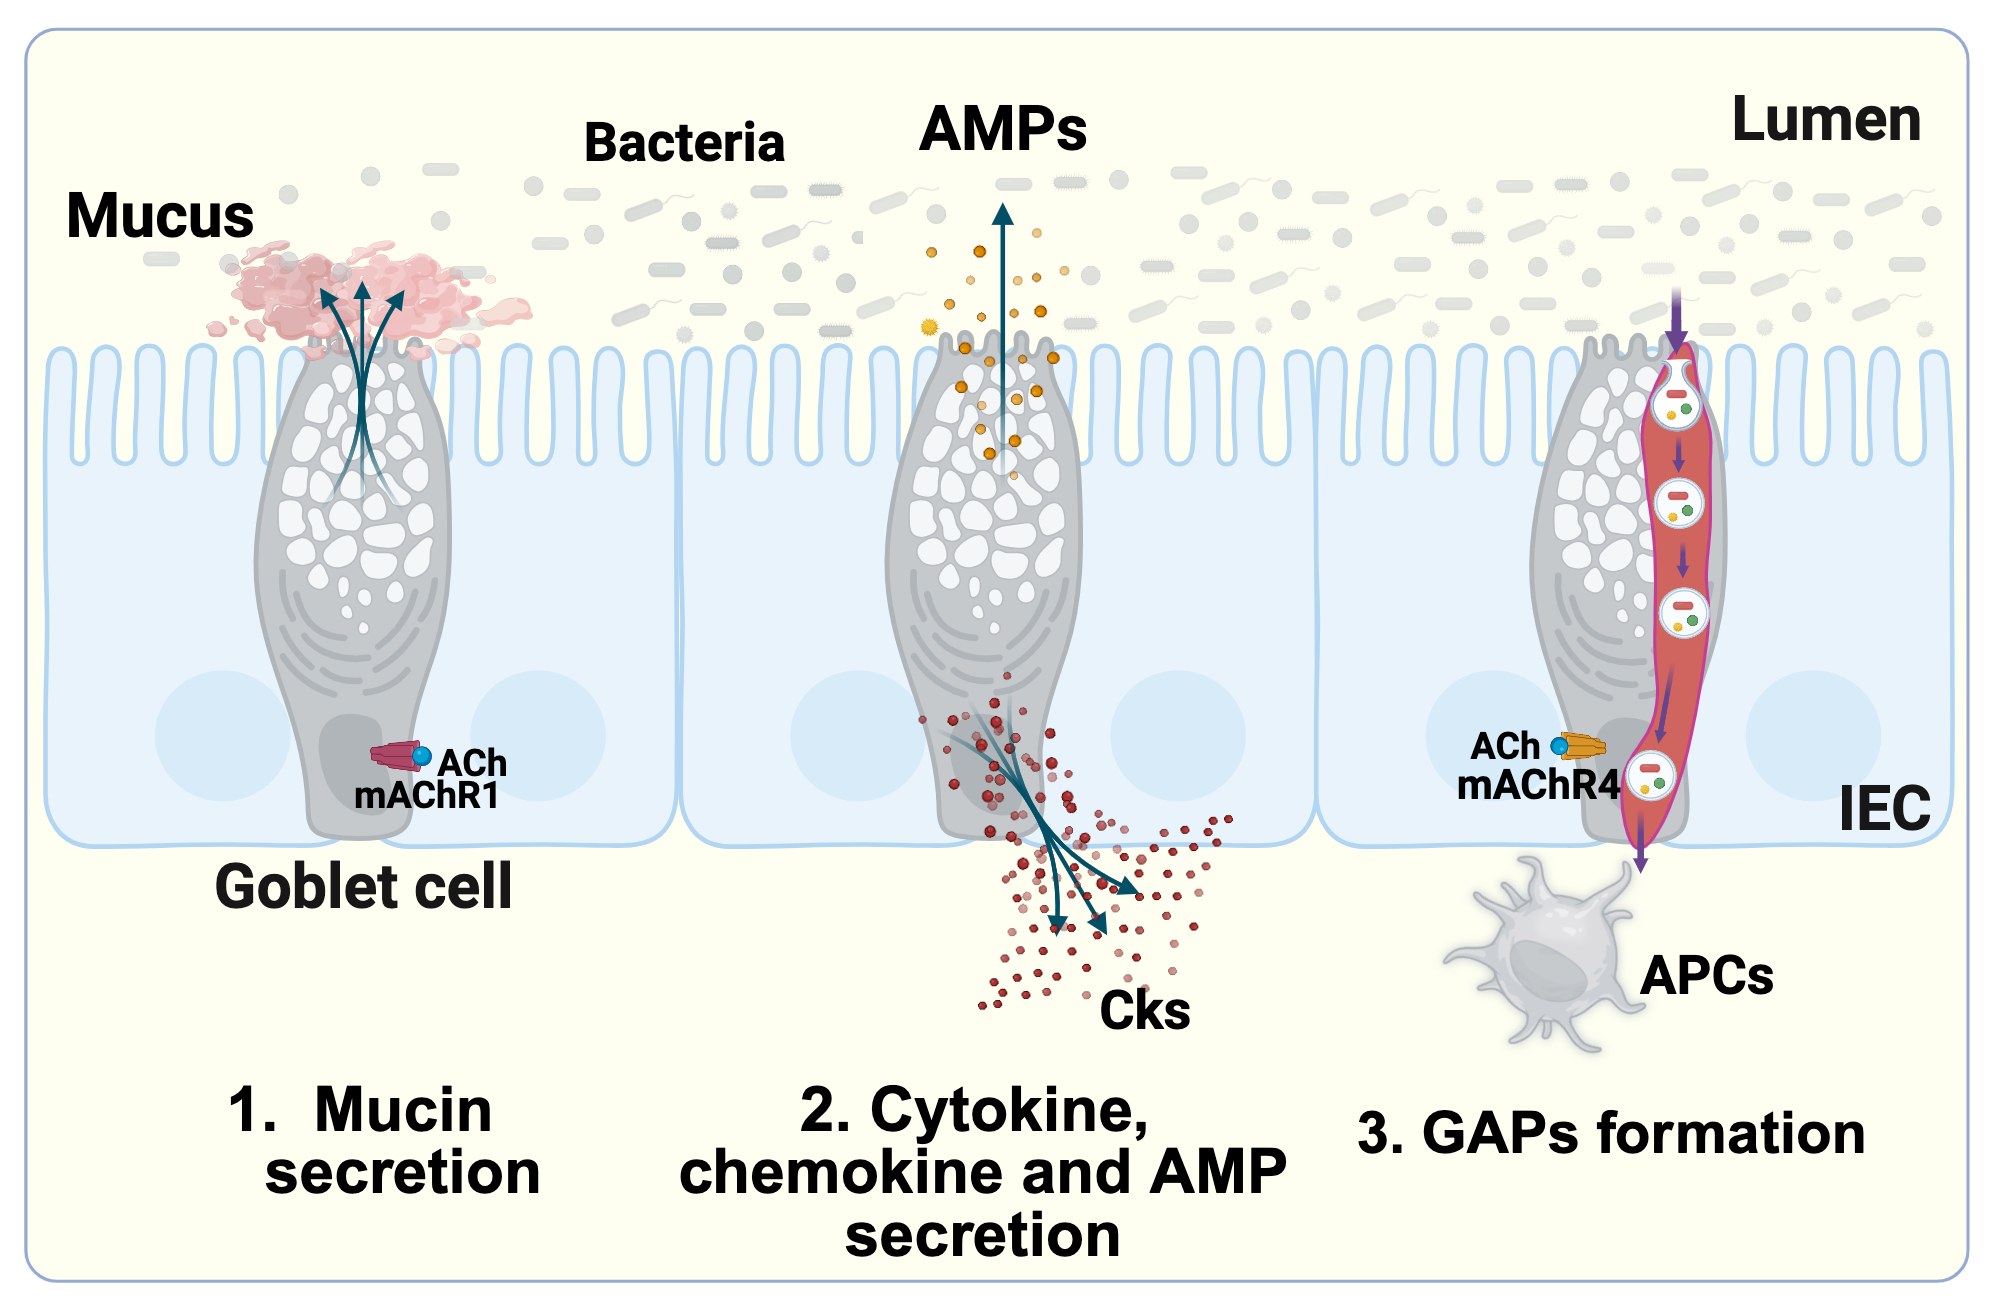

Goblet cells produce mucin glycoproteins that form a protective mucus layer over the intestinal epithelium, which is primarily composed of the secreted mucin MUC2. In addition to mucin secretion, goblet cells play a central role in immune regulation. They secrete cytokines, chemokines, and antimicrobial peptides, including resistin-like molecule beta (RELMβ) and trefoil factor family peptide 3 (TFF3), which help maintain mucosal homeostasis. Furthermore, goblet cells contribute to immune surveillance by sampling luminal antigens and delivering them to antigen-presenting cells (APCs) in the lamina propria through specialized structures known as goblet cell-associated antigen passages (GAPs), thereby promoting adaptive immune responses.

GAPs are specialized passages that function as gateways, facilitating the controlled delivery of luminal antigens to APCs in the lamina propria. By enabling selective communication between the intestinal lumen and the immune system, GAPs play a key role in promoting immune tolerance to dietary antigens, while also training it to recognize and respond effectively to harmful pathogens.

Key Features and Mechanisms:

- GAP Formation and Function: GAPs form mainly in the small intestine, triggered by acetylcholine (ACh) binding to muscarinic ACh receptors (mAChR4 in small intestine, mAChR3 in distal colon). This process involves endocytic vesicle trafficking dependent on PI3K, actin, and microtubules. Luminal antigens are translocated across goblet cells via two distinct mechanisms: endocytic vesicle-mediated uptake and transcytosis, enabling their delivery to lamina propria-APCs (APCs) for immune surveillance. GAPs are closed during enteric infection, such as Salmonella typhimurium, to prevent pathogen dissemination and limit responses to dietary antigens.

GAP-Induced Immune Cascade Restores Protection. We define a novel and critical molecular mechanism involving GAP generation, which samples luminal antigens and initiates a protective, APC-mediated immune response. APCs secrete IL-23, promoting IL-22 production by ILC3s. IL-22 then acts on IECs and Paneth cells to induce antimicrobial Reg3 lectins. In summary, the GAPs → LP-APCs → IL-23 → ILC3s → IL-22 → Reg3 axis limits mucosa-associated bacteria, prevents bacterial translocation to the liver, and protects against ethanol-induced liver injury.

GAPs deliver luminal antigens to lamina propria antigen-presenting cells, educating the intestinal immune system and stimulating REG3B/G antimicrobial peptides. Figure created with a license from BioRender. -